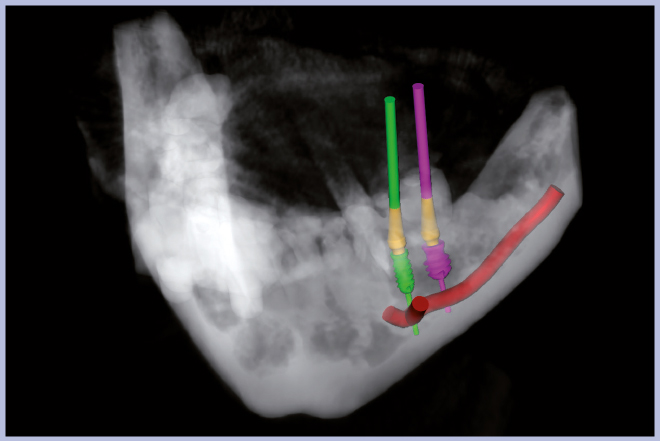

Per riabilitare la masticazione del terzo quadrante, con osso gravemente atrofico, si procede allo studio del caso con esame radiologico 3D e posizionamento virtuale di impianti Exacone® Leone. La prima valutazione è stata eseguita con il software dell’apparecchio radiografico Cone Beam presente in studio. Dopo aver verificato che la quantità di osso residuo fosse sufficiente all’inserimento di due impianti, seppur di dimensioni ridotte, in sede 3.5 e 3.6 senza l’ausilio di tecniche di rigenerazione ossea (Figg. 1-3), si richiede al laboratorio di confezionare una mascherina radiologica con ceratura diagnostica radiopaca e repere standardizzato a livello incisale come da protocollo Leone (Figg. 4, 5). Si verifica quindi clinicamente l’assenza di mobilità della mascherina dopo il posizionamento nel cavo orale del paziente (Figg. 6, 7). Si effettua una CBCT con la mascherina in posizione e l’esame viene inviato in formato DICOM all’azienda Leone assieme al modello master della paziente. L’azienda provvede quindi ad inviare agli Autori il software 3Diagnosys (software di progettazione) in licenza monopaziente con caricati i file DICOM ricevuti; il software viene quindi utilizzato per la progettazione definitiva del caso (Figg. 8-12).

- Figg. 8-12 – Pianificazione implantare con software 3Diagnosys Leone

- Fig. 9

- Fig. 10

- Fig. 11

- Fig. 12